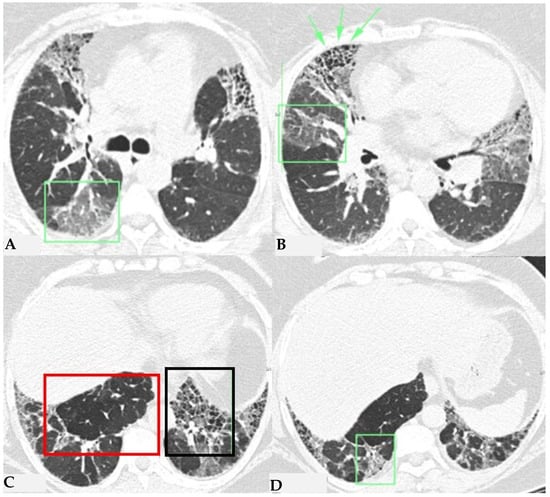

Figure 3.

FHP: chest HRCT (A–D). Upper lobes and right lower lobe are characterized by areas of increased GGO density (green box: (A,D)) within which well-defined bronchiectasis and traction bronchiolectasis, indicative of established fibrotic damage, are observed (green arrows: (B)). Lower lobes extensively affected by mixed alterations, expressing damage to small airways with areas of reduced attenuation suggestive of air trapping (red box: (C)), and confirmed fibrotic damage with honeycombing and traction bronchiectasis (black box; (C)). Pattern of FHP.